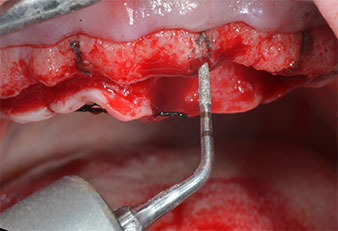

A flame-shaped, diamond-coated piezoelectric instrument (Piezomed I1) was used to mark the implant positions and to perform pilot preparation (Fig. 3). Care was taken to use an up and down movement, with reduced power, full irrigation and low pressure (below 300 g). Next a pilot instrument (Piezomed I2A/I2P) was applied for the initial 2 mm diameter enlargement of the implant sites (Fig. 4), followed by a 3 mm insert (Fig. 5).

In case of dense bone the whole instrument sequence including the intermediate instruments Piezomed Z25P and Z35P should be used to widen the osteotomies before the next enlargement step.

They are also indicated for preparation near the sinus membrane in connection with internal augmentation procedures or when there is less than 4 mm of residual bone height.

In the present case the Z25P and Z35P instruments were not used due to the relatively soft posterior bone, which was easily managed with the I3A/I3P.